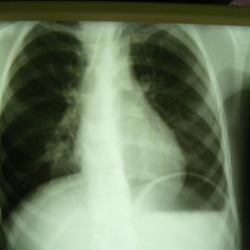

Женщина средних лет пришла исключить пневмонию слева. Я написал, что вижу инфильтрацию слева в S8. А вы как считаете? Сама пациентка отмечает кашель, незначительную болезненность в левом боку.